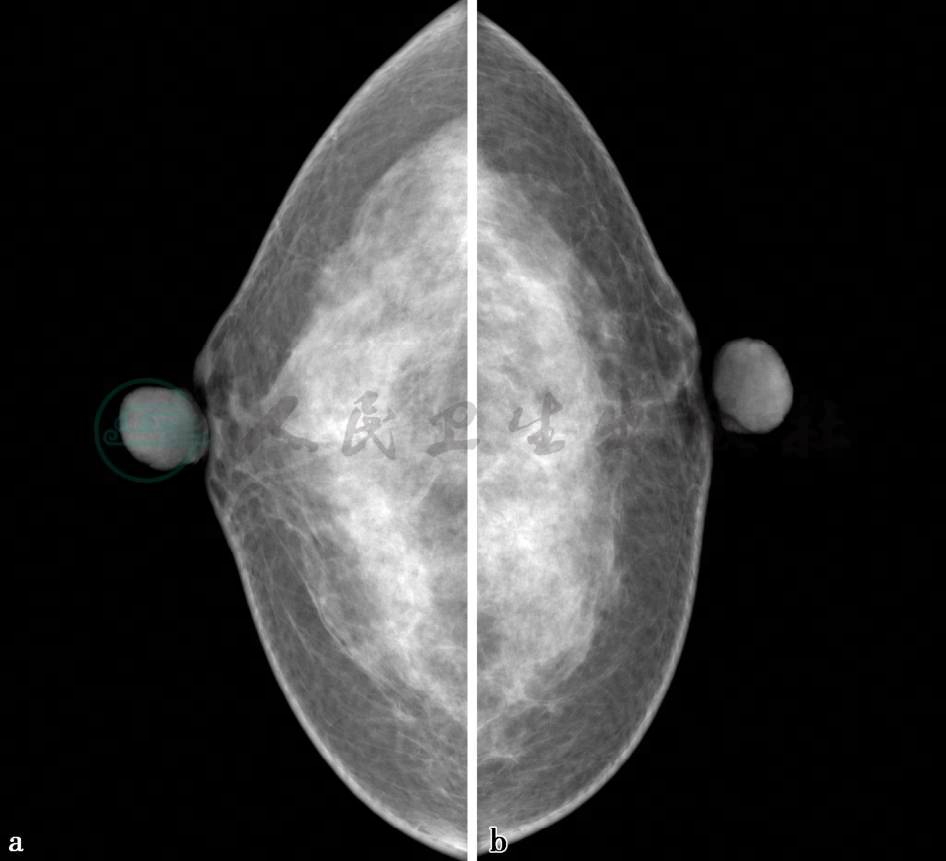

X线及二维超声图。

图1 图1a,右乳X线头尾位。图1b,左乳X线头尾位。图1c,右乳X线内外斜位。图1d,左乳X线内外斜位。图1e,左乳病变二维超声图。超声显示左乳腺中上方1.5cm×0.9cm低回声区,边界不清,内部回声不均匀,其后方可见声影